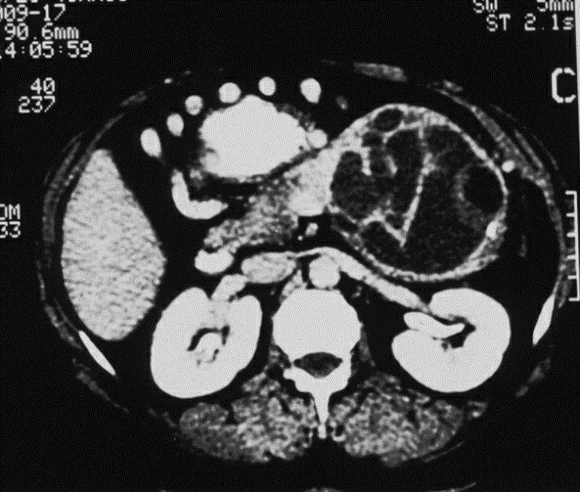

Neoplasia Cística Mucinosa – Cistadenoma Mucinoso

Os cistos podem ser únicos ou multiloculares com diâmetro de 1 a 3,5cm. Estes tumores são consideradas lesões benignas com potencial de malignização menor que as lesões papilíferas intraductais.

Diferentemente das neoplasias intraductais produtoras de mucina não se comunicam com o ducto pancreático. Tipicamente não apresentam sintomas e são achados em exames de imagem indicados por outra razão.

Tumor cístico (composto de líquido e muco) do pâncreas que pode ser:

- maligno na forma de cistoadenocarcinoma mucinoso. São formados de epitélio colunar espesso composto por estroma semelhante ao ovário (“ovarian-type stroma”).

Características:

- acomete mais mulheres jovens e meia idade entre 30 a 45 anos;

- a maioria se encontra no corpo e cauda pancreática;

- 40% ou mais desses tumores tem componente de malignidade invasiva no tempo de seu diagnóstico;

- na tomografia ou ressonância aparecem como tumores redondos, bem encapsulados, septos grosseiros e cistos grandes, calcificações na periferia do tumor e estão mais presentes quando existe malignização (designadas de “Egg-Shell” ou casca de ovo ). São sinais de preocupação também, a presença de nódulos intracísticos, obstrução biliar, invasão de gordura peri-pancreática e ascite;

- na colangiopancreatografia não há comunicação do cisto com Ducto de Wirsung;

- a Eco-Endoscopia com bíopsia e aspirado do liquido mostra rico em mucina (muco assim como as células, pode conter atipias) e tem valores altos de marcadores como CEA, CA 19,9 (abaixo de 37,0) com níveis baixos de amilase.